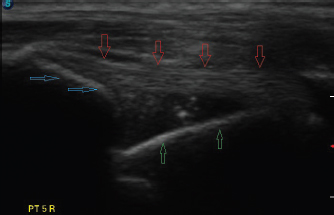

Fig. 5. Longitudinal ultrasound image of a transected biceps tendon. The intact tendon is indicated with red arrows and the point of transection with a green arrow.

Fig. 6. Persistent remnant of tissue following incomplete transection. This fragment was friable and thought not to likely diminish the procedure outcome in an actual clinical case.

Ultrasound verification of complete tendon transection was demonstrated if the tendon remained lax proximally as it spanned the glenohumeral joint, even though the limb position had not changed (Fig. 4). The tendon’s appearance, following transection, could be compared to the images taken earlier, as needed. Longitudinal and transverse imaging was also performed over the transection site to demonstrate a complete absence of tendon fibers (Fig. 5). If incomplete transection was observed, the ultrasound probe was removed and the procedure repeated until complete transection occurred. On two occasions there was discordance between the second researcher’s assessment of the complete transection based on palpation, compared to ultrasound findings. On both those occasions, it was elected to proceed with dissection rather than resume the transection.